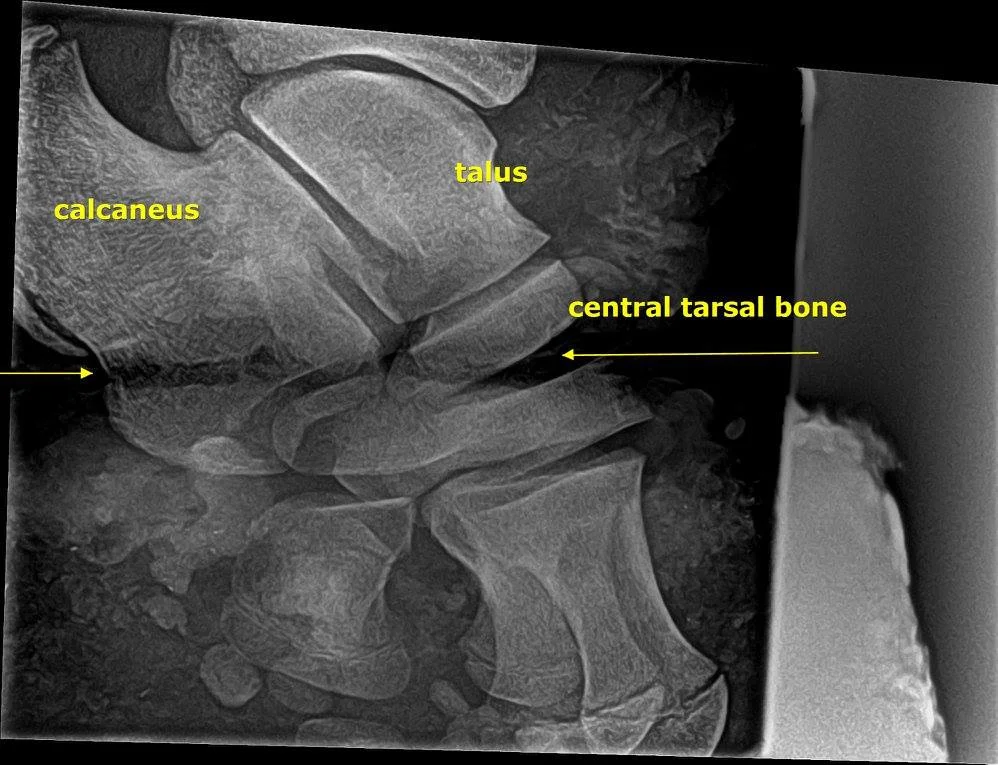

In this case it was a young male elephant suffering from a snare around his back leg and was literally slowly sawing his foot off. After finding  the young elephant he was darted and tended to by the AWARE vets. The snare was removed and an X-ray was taken. The X-Ray showed considerable damage and if not tended in time the young elephant would have died from infections. The vets treated the elephants with anti imflammatories and an ultra long acting antibiotics. The AWARE vets both thought the young elephants wound would heal well with time.

Dr Lisa Marabini x-raying the injured leg. We were part of donating the portable x ray machine to AWARE most importantly my friend/brother in law Brian Rogers.